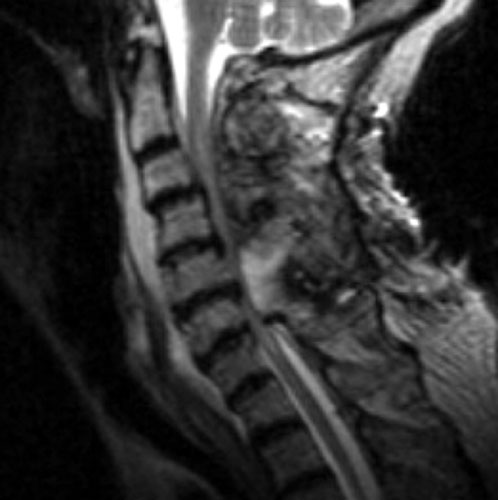

A B C

Non-enhanced sagittal T1 (A), sagittal T2 (B) and axial T1 images demonstrate a large fluid collection, predominantly low signal on T1, bright on T2 with a few areas of T1 hyperintesity mixed within. These constellation of findings are consistent with a post-operative epidural hematoma with blood products of various ages. There is severe severe spinal canal stenosis at C3-4, and very severe spinal canal stenosis at C4-5 and C5-6. The cord is markedly flattened in the anterior-posterior dimension, to approximately 2-3 mm secondary to mass effect from this fluid collection. There is abnormal T2 weighted hyperintensity within the substance of the cord at the C5-6 and C6-7 levels, consistent with some edema.